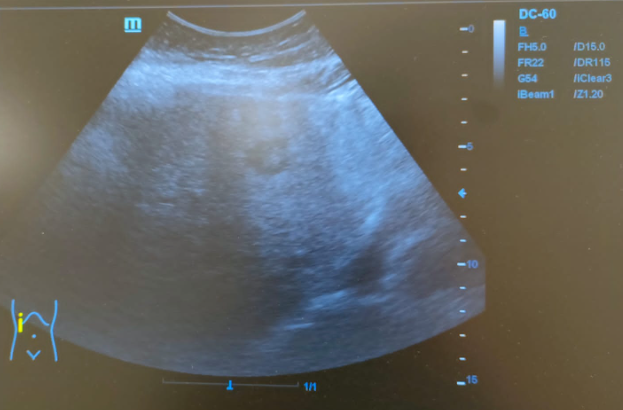

Hallazgos ecográficos

Hígado de tamaño normal, contornos ligeramente nodulares, alteración de la ecoestructura compatible con hepatopatía crónica. Nódulo hipoecoico de contornos irregulares en lóbulo hepático izquierdo de 16x24mm sin captación Doppler.

Tras realizar la ecografía en el CAP se observó un nódulo hipoecoico de contornos irregulares. Entre los diagnósticos diferenciales posibles que justificasen el patrón de colestasis se encontraba el CHC o una metástasis, por lo que se realizó una prueba complementaria que confirmó el diagnóstico de CHC.